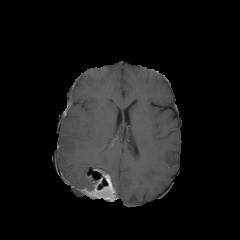

Case 1: Hallucination and mitigation in MM-VisHal [Uncaptioned image] Question: “Is there evidence of brain edema in the image?” Ground truth: “Yes.” LLaVA-Med: “No, there is no evidence of edema in the brain in the MRI.” Ours: “Yes, there is evidence of edema in brain tissue.” Case 2: Hallucination and mitigation in CXR-VisHal [Uncaptioned image] Question: “Does the image show any signs of cardiomegaly?” Ground truth: “Yes.” LLaVA-Med: “The chest X-ray does not show any signs of cardiomegaly.” Ours: “Yes, the chest X-ray shows signs of cardiomegaly.”

Table 7: Examples of hallucination and mitigation cases.

4.7 Case Study for Hallucination and Mitigation

Table 7 presents case studies from close-ended datasets on visual misinterpretation hallucinations. We provide the produced replies from our technique and baseline approach in Cases 1 and 2 to visually show the efficacy of our strategy. our method which enhances visual grounding through attention modification, successfully corrects the hallucinated responses. While it does not work for LLaVA-Med. This study reinforces our findings that our mitigation method exhibit strength in hallucination mitigation, emphasizing the need for task-specific approach to improve Med-LVLM performance.